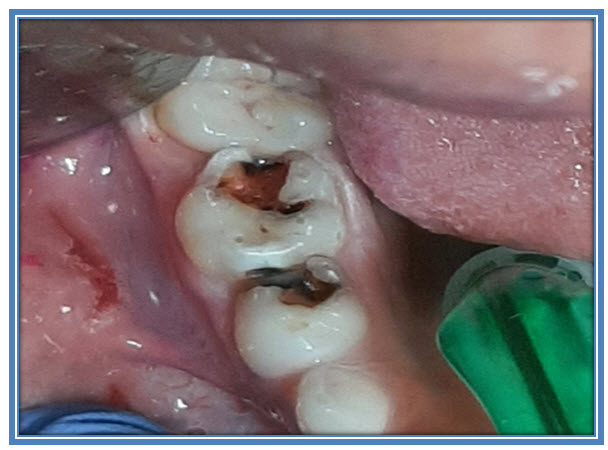

Kontakti se kod bočnih mlečnih zuba formiraju do 30 meseca deteta, do kada bi trebalo da izniknu svi zubići. Tada se rizik za razvoj karijesa prebacuje sa prednjih zuba na bočne. Prvo če se razvijati karijes na griznim površinama, a u naredne dve godine i na bočnim i ta dva procesa su često povezana i spajaju se (Slika 2.).

Bočni karijes na mlečnim zubima (posebno od očnjaka pa do „petice“) je izuzetno podmukao jer se klinički (golim okom) ne može registrovati u početnoj fazi!!! Topljenje (izvlačenje minerala) tvrdih zubnih tkiva se širi u dubinu i podriva greben (prelaz između grizine i bočne površine zuba). Tkivo zuba u jednom trenutku puca, stvara se defekt koji je prilično komplikovan za oporavak sa plombama (Slika 2.). Prodiranje karijesnog razaranja, dok se ne stvori defekt. je generalno spor proces. Na bočnim površinama mlečnih zuba to može da iznosi i preko dve godine, a kod stalnih i do šest godina. Detaljnije

Kod mlečnih bočnih zuba, često, kada se primeti pucanje grebena, proces karijesa je već prilično prodro u dubinu i već zahvatio meko tkivo u unutrašnjosti (zubna pulpa, „živac“). (Slika 3.)